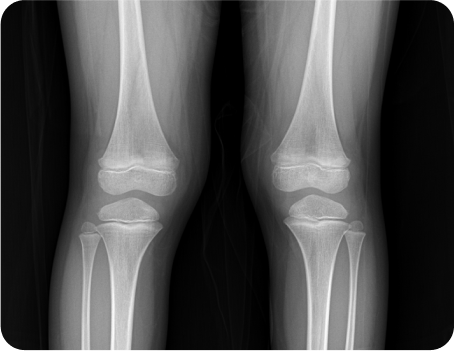

몸은 체형이 휘거나 구부정한 경우 성장판에 자극을 충분히 받지 못하거나 관절에 무리한 자극이 가게 되어 뼈의 성장 불균형 또는 장애를 초래하게 됩니다.

성장판 활성도 및 호르몬 검사 등의 기능적인 검사부터 체형과 측만증, 휜 다리 등의 구조적인 검사까지 놓치지 않으니까

체형교정

안짱걸음 및 측만증, 거북목, 휜 다리, 평발을 교정해 숨은 키를 찾아내고 성장의 가속도를 더함

성장추나

척추와 골반 무릎을 늘려주어 성장판 활성화,

틀어진 골반과 척추를 교정해 근육 긴장을 이완